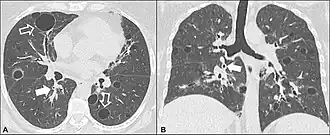

- КТ высокого разрешения, на которой выявляют утолщение межальвеолярных перегородок, центролобулярные узелки, кистозные полости и небольшие участки консолидации легочной ткани. Для КТ картины характерны участки пониженной прозрачности паренхимы по типу «матового стекла».